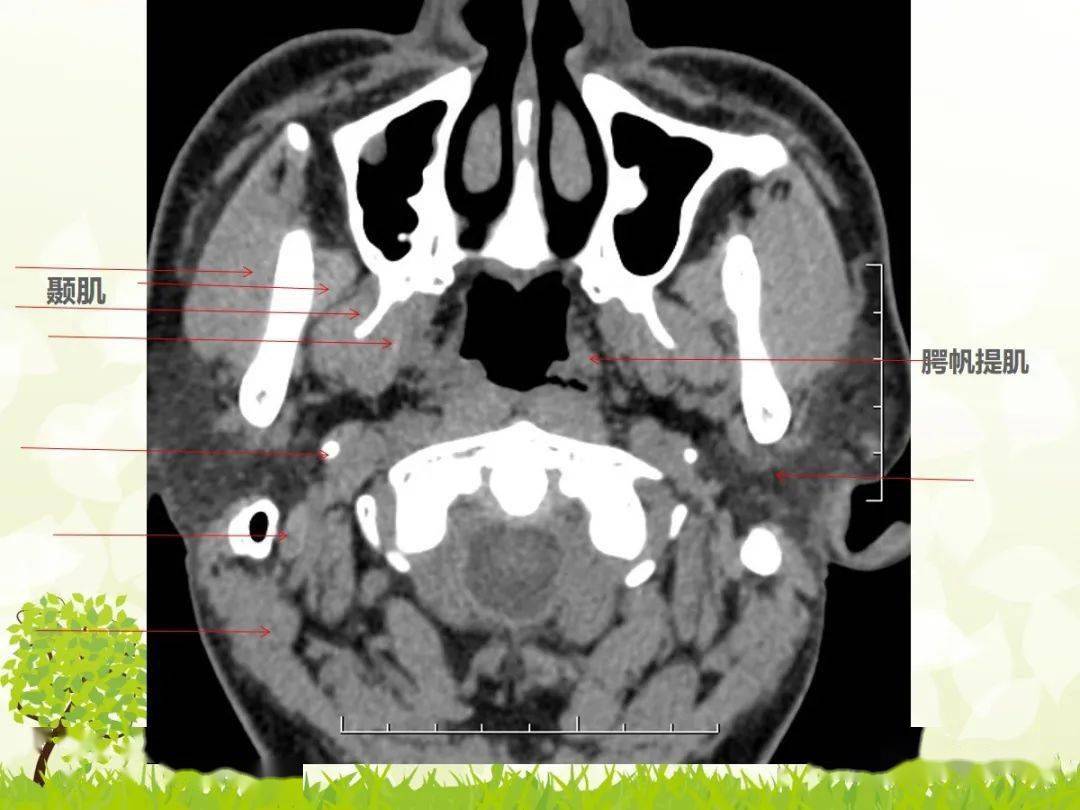

口咽解剖图ct

口咽位于腭帆游离缘至会厌上缘之间.向前经咽峡与口腔相通.